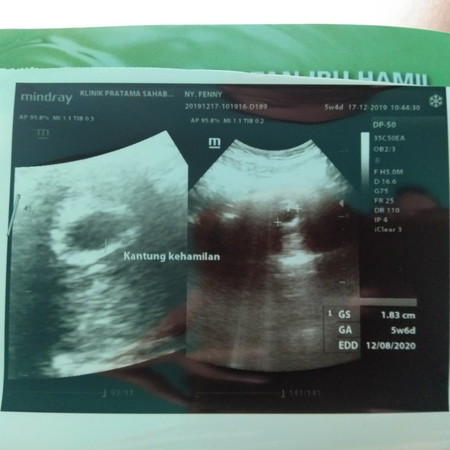

5w6d itu keterangannya yg GA bundaaaaaaa

Itu lho GA 5w